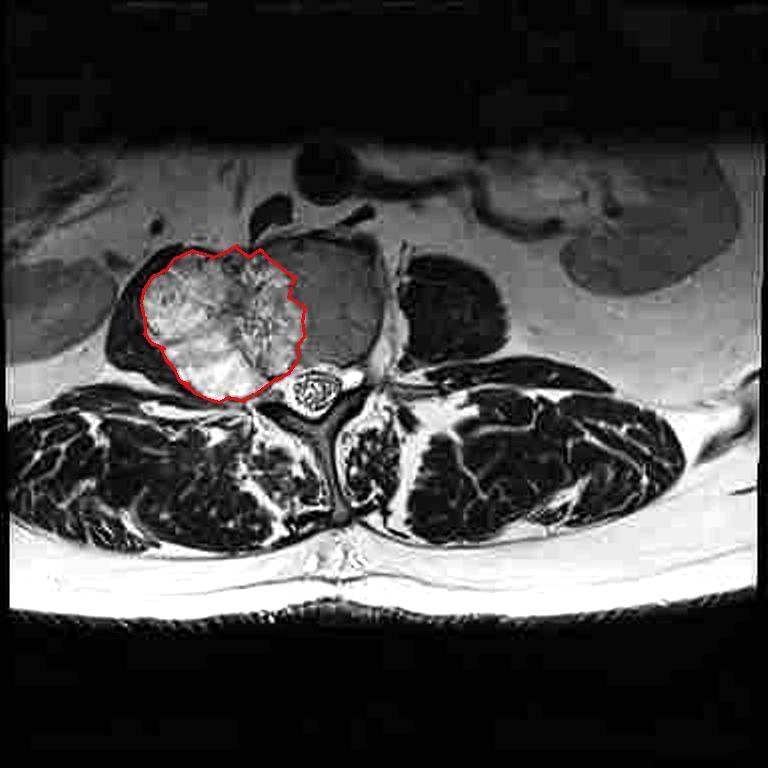

My friends. It seems that life is kicking my ass. I have a malignant (chordoma) tumor on my L2 vertebra. It's big and ugly and it is causing so much pain that I can no longer walk. I can't stand longer than a few seconds, maybe a minute, before I have to sit down.

This is a very rare cancer and there aren't any curative therapies. It is slow growing so - hopefully - after removal and post-operative recovery I can live a few years in peace. My workplace is giving me FMLA for the recovery period, but as many of you know, FMLA is UNPAID after your sick time and vacation pay are spent.